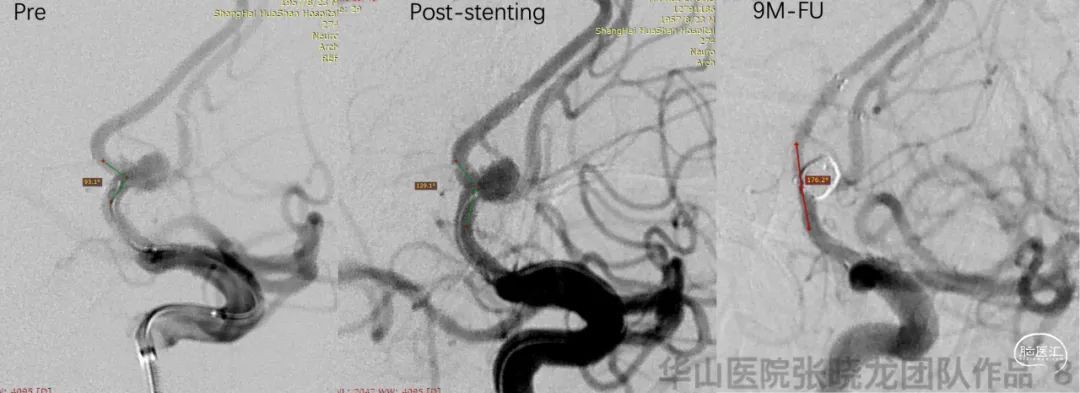

Video 1. The aneurysms were not relapsed and parent artery was patent by 9 month follow up.

视频 1. 9个月随访动脉瘤无残余及复发,载瘤动脉通畅。

视频 2. 9个月随访前交通微小动脉瘤未见显影。

图 8. 载瘤动脉被Solitaire支架拉直明显。

• A tiny irregular anterior communicating aneurysm was treated by stent remolding technique because coils may be difficult to insert into. A Solitaire stent was selected. The small aneurysm was invisible because the parent artery was straightened by a Solitaire stent.